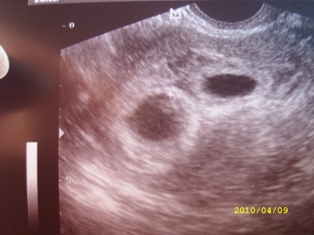

Megjöttünk az UH-ról K ügynöktől! 7 hetesek vagyunk.